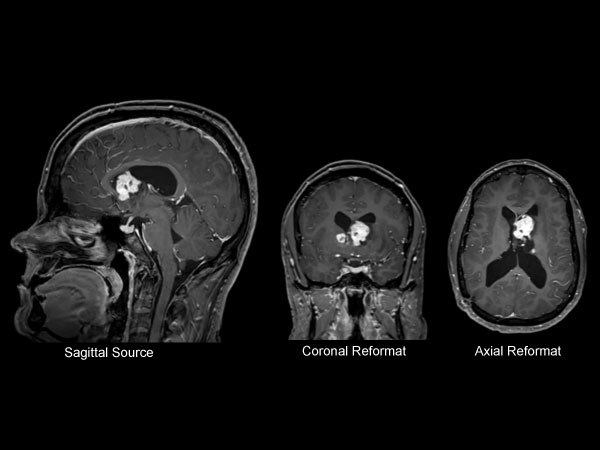

Sagittal T1W IR TSE

Axial T1W IR TSE